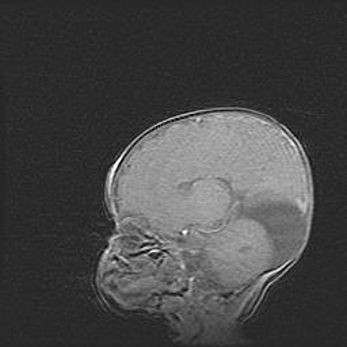

Подострая гематома правой гемисферы мозжечка.

Наружная гидроцефалия.

Возраст: 15 дней

Вес: 3100 г

Пол: женский

Окружность головы: 37 см

Срок гестации: 35-36 недель

При открытой наружной форме гидроцефалии у новорожденных расширяются и переполняются субарахноидные пространства.

Кровоизлияния в мозжечок имеют две клинико-анатомические формы: полушарные гематомы и кровоизлияния в червь.

К появлению этой патологии может привести: повреждения головного мозга, возникающие в результате асфиксии и гипоксии плода при беременности, или травмы во время родов. Редко гематома мозжечка может быть результатом первичной коагулопатии и сосудистой мальформации, диссеминированном внутрисосудистом свертывании, изоиммунной тромбоцитопении.